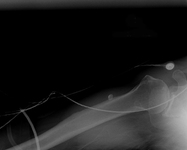

Axillary lateral of a shoulder with a missed posterior dislocation: humeral head clearly is not reduced and is locked on the posterior rim of the glenoid

Personal collection of Dr Paul Novakovich